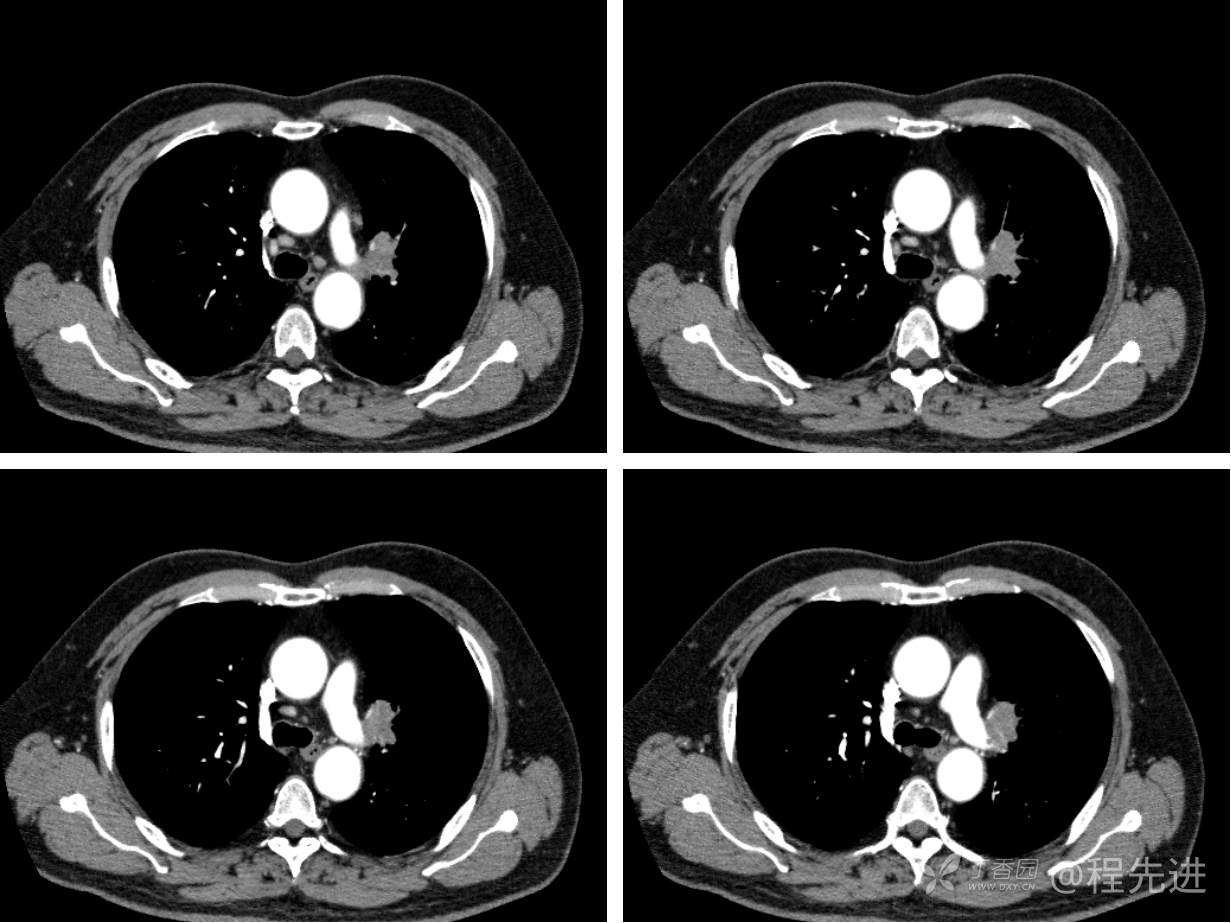

现病史概要:患者入院前约半月无明显诱因下出现咳嗽、胸闷症状,无明显发热症状,咳少量白痰,无明显咯血、喘息、头晕等不适,就诊我院查胸部CT示上纵膈肿物,左肺上叶支气管内肿物,现为行进一步治疗收入胸外科,患者近来饮食睡眠尚可,二便如常。